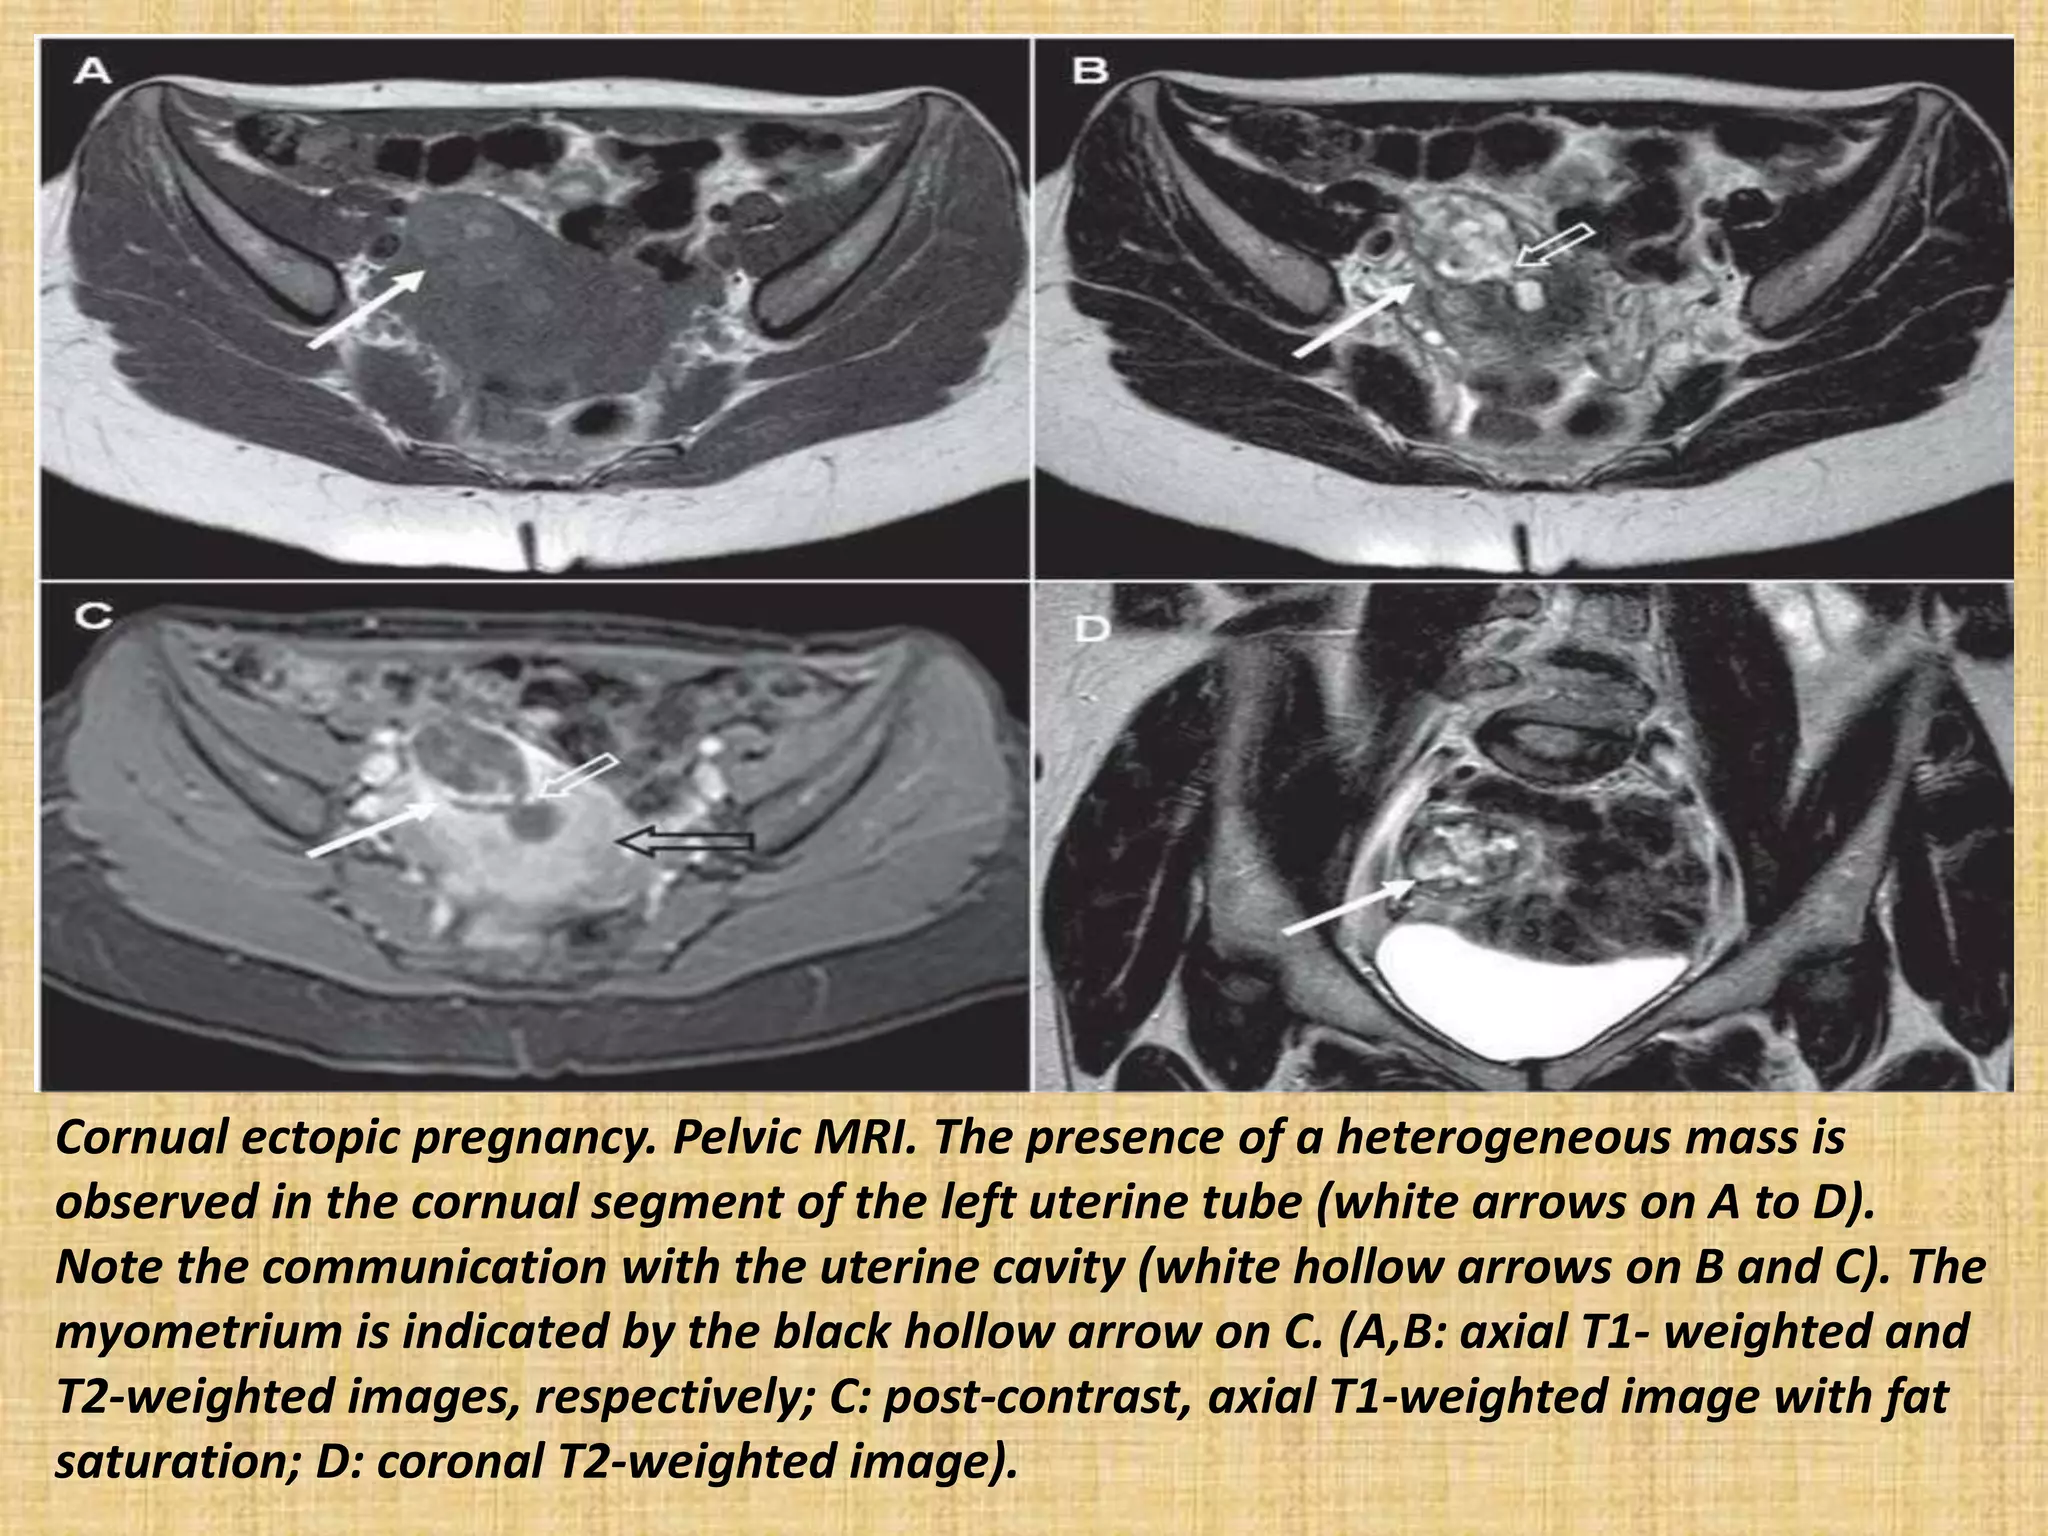

Cornual ectopic pregnancy. Pelvic MRI. The presence of a heterogeneous mass is

observed in the cornual segment of the left uterine tube (white arrows on A to D).

Note the communication with the uterine cavity (white hollow arrows on B and C). The

myometrium is indicated by the black hollow arrow on C. (A,B: axial T1- weighted and

T2-weighted images, respectively; C: post-contrast, axial T1-weighted image with fat

saturation; D: coronal T2-weighted image).

Cornual ectopic pregnancy.Pelvic MRI. The presence of a heterogeneous mass is observed in the cornual segment of the left uterine tube (white arrows on A to D). Note the communication with the uterine cavity (white hollow arrows on B and C). The myometrium is indicated by the black hollow arrow on C. (A,B: axial T1- weighted and T2-weighted images, respectively; C: post-contrast, axial T1-weighted image with fat saturation; D: coronal T2-weighted image).